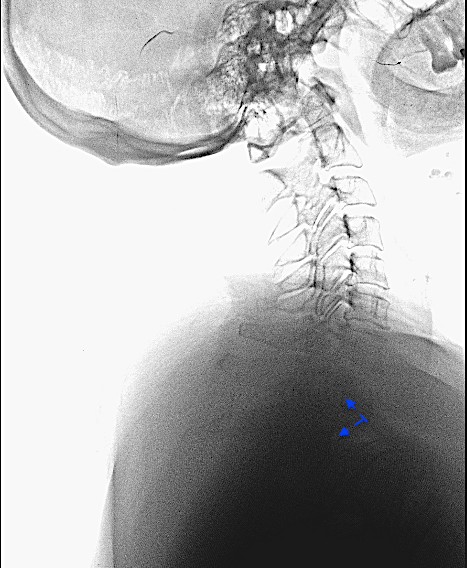

CASO CLÍNICO 1: HERNIA DISCAL TH1-TH2 MIGRADA CAUDALMENTE (con engrosamiento calcificado de LVCP hasta Th2-Th3).

Paciente de 58 años con dolor radicular refractario de >6 meses en MSD, acompañada de pérdida de fuerza en la musculatura intrínseca y atrofia muscular. EMG presenta afectación severa crónica en raíces C7-C8-Th1 derechas.

Obsérvese HDTh1-Th2 con migración caudal retrosomática (Th2)

Obsérvese el engrosamiento de LVCP de aspecto calcificado

El compromiso anterior del canal (a pesar de la radiculopatía severa en MSD) me obliga a plantearme un abordaje anterior con posibilidad de ampliar el campo a través de una esternotomía.

En las imágenes de arriba se aprecian las dificultades anatómicas del abordaje anterior.